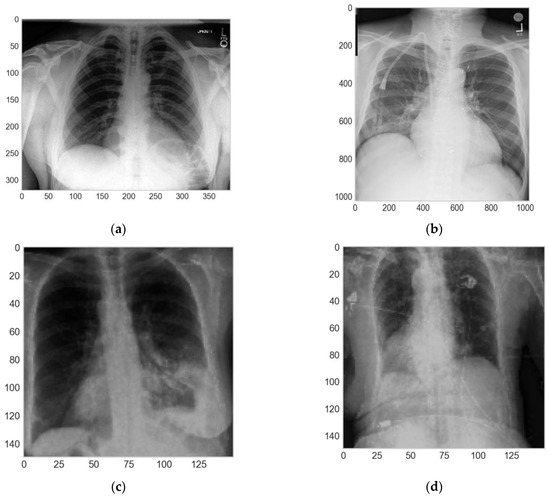

2.7. CNN Training

We used a personal computer with Intel® Core i7™—RAM 8GB and Nvidia® Geforce GTX™ 1050. The operated system was Windows® 10, professional edition. The dataset developed for the work was composed of 16,372 images where around 86% were from [20] and about 14% were from [21]. The images were classified in five different lung diseases, i.e., atelectasis, cardiomegaly, consolidation, edema, and pleural effusion (Figure 4).

Figure 4.

Chest X-rays (CXRs) of the five different lung diseases used in this work: (a) atelectasis; (b) cardiomegaly, (c) consolidation, (d) edema; and (e) pleural effusion.